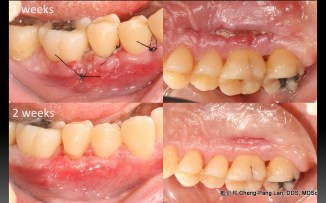

Root Coverage – Coronally Advcanced Flap with Connective Tissue Graft- Case B

Recipient Site: Harris’s technique, 1992